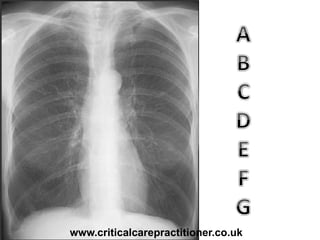

TECHNICALS

AIRWAY

BONES

cARDIAC

DIAPHRAGM

GASTRIC BUBBLE

EQUAL LUNG FIELDS